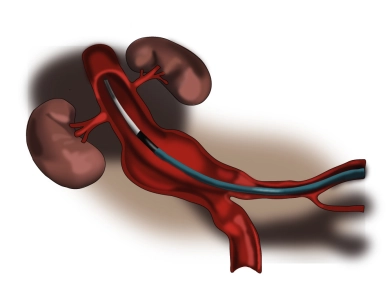

Aorta y lecho vascular pélvico

EVAR – Reparación endovascular de un aneurisma de aorta abdominal (prótesis en Y)